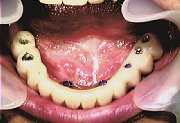

症例1 インプラント

62才、女性。35年間下顎総義歯で悩んでいた。上顎は天然歯。